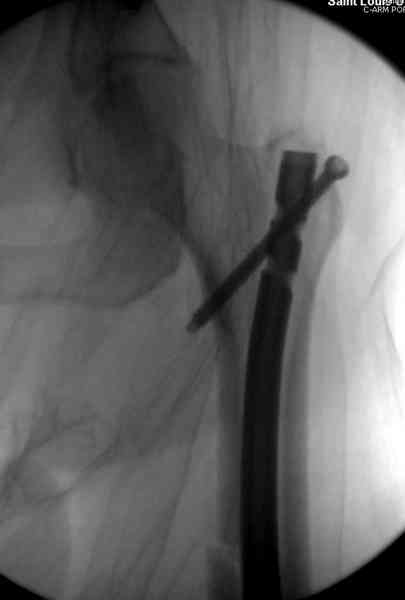

Здесь представлены снимки больного 65 лет, поступившего с диагнозом перелом

бедра после автоаварии.

В первый же день произведено антеградное штифтованием DePuy Trochanteric Nail.

На второй день (7) обнаружен пропущенный перелом,

сделаны Компьютерная Томограмма

и проведены шурурпы через и спереди штифта без удаления.

Послеоперационные снимки